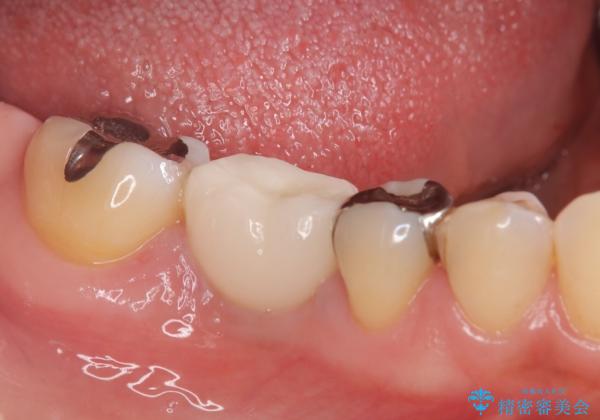

- 右下奥歯が虫歯で被せ物が取れてしまい、また噛めるようにしたいとのことで来院されました。

虫歯が大きく、歯を保存することが難しい状態でしたので、抜歯してインプラント治療を行うこととなりました。